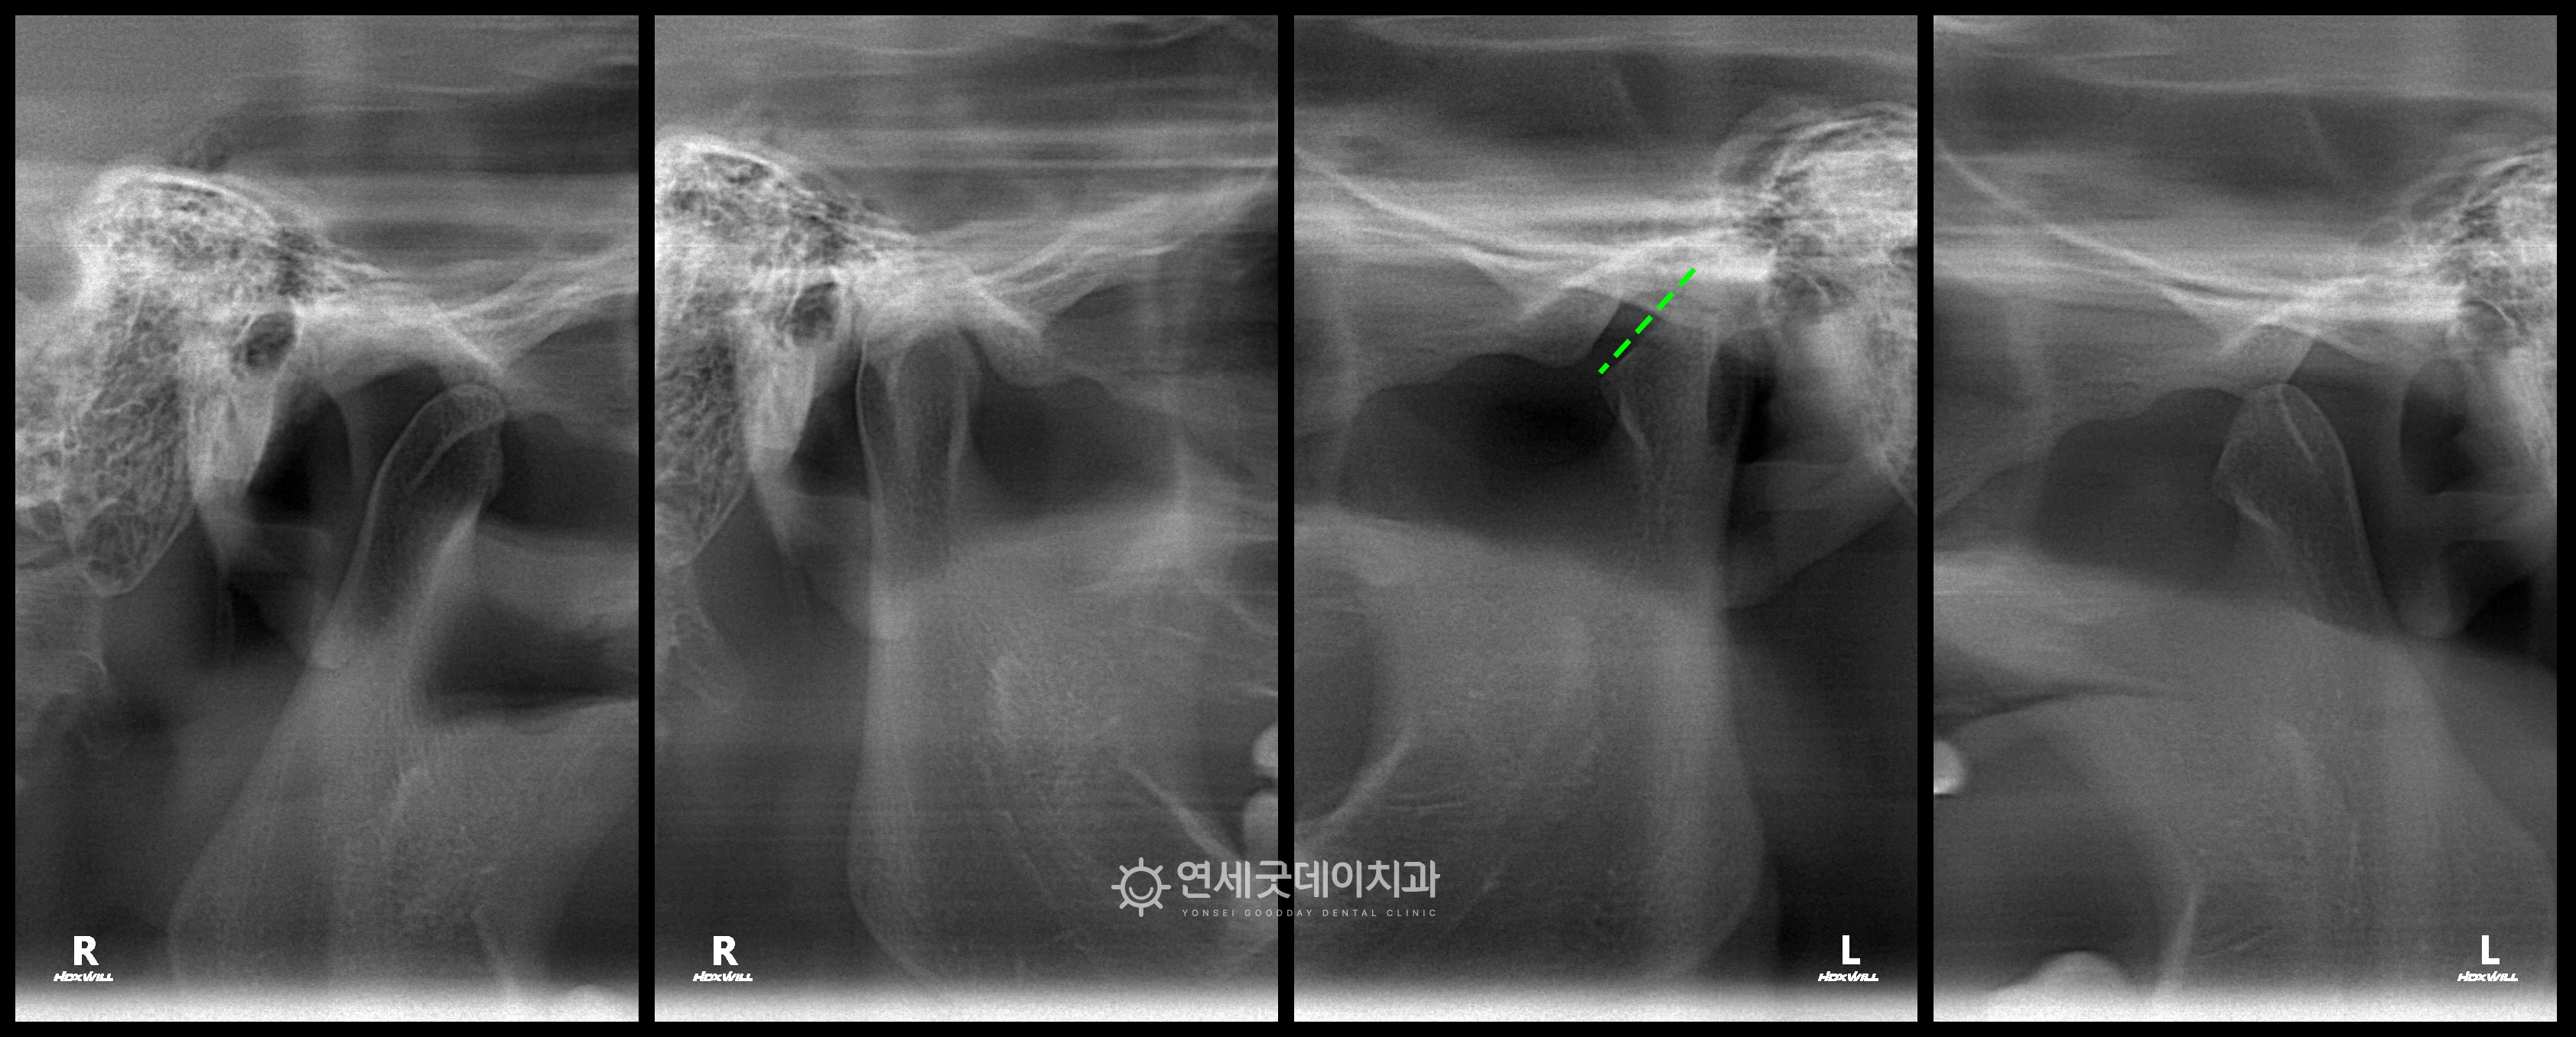

▲ 턱관절 방사선촬영 (촬영시기 : 2023년 9월)

환자분의 턱관절 방사선을 보면, 왼쪽 턱관절이 많이 녹은 상태로 또한 턱관절과 함께 경도의 개방교합도 관찰되었는데요. · Option ① 트랙션 치료 (100% 교합 개선은 한계가 있음) 총 3가지의 치료옵션을 제안드렸으며